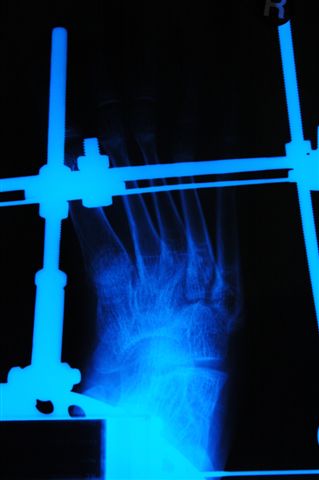

[Ortho] joint distraction, chondrolysis

attached x rays of 15yrs old boy metioned earlier